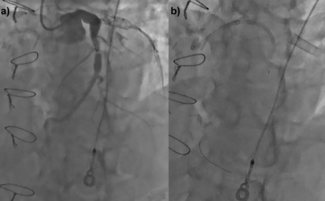

Clinical Images

Barbara D. Lawson, MD; Issa Kutkut, MD; Zachary M. Gertz, MD; Babar Khan, MD; Stephen O. Hunley, MD

When dislodged stents remain on the coronary wire, the wire can be snared outside of the body. These two cases demonstrate the use of the presnaring technique to retrieve dislodged coronary stents when the stent remained on the coronary wire.